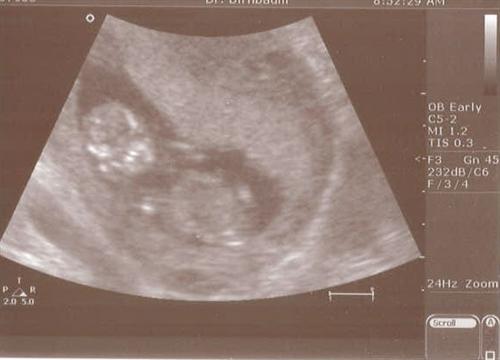

Our baby

Dec2008Baby

12/10/08

5